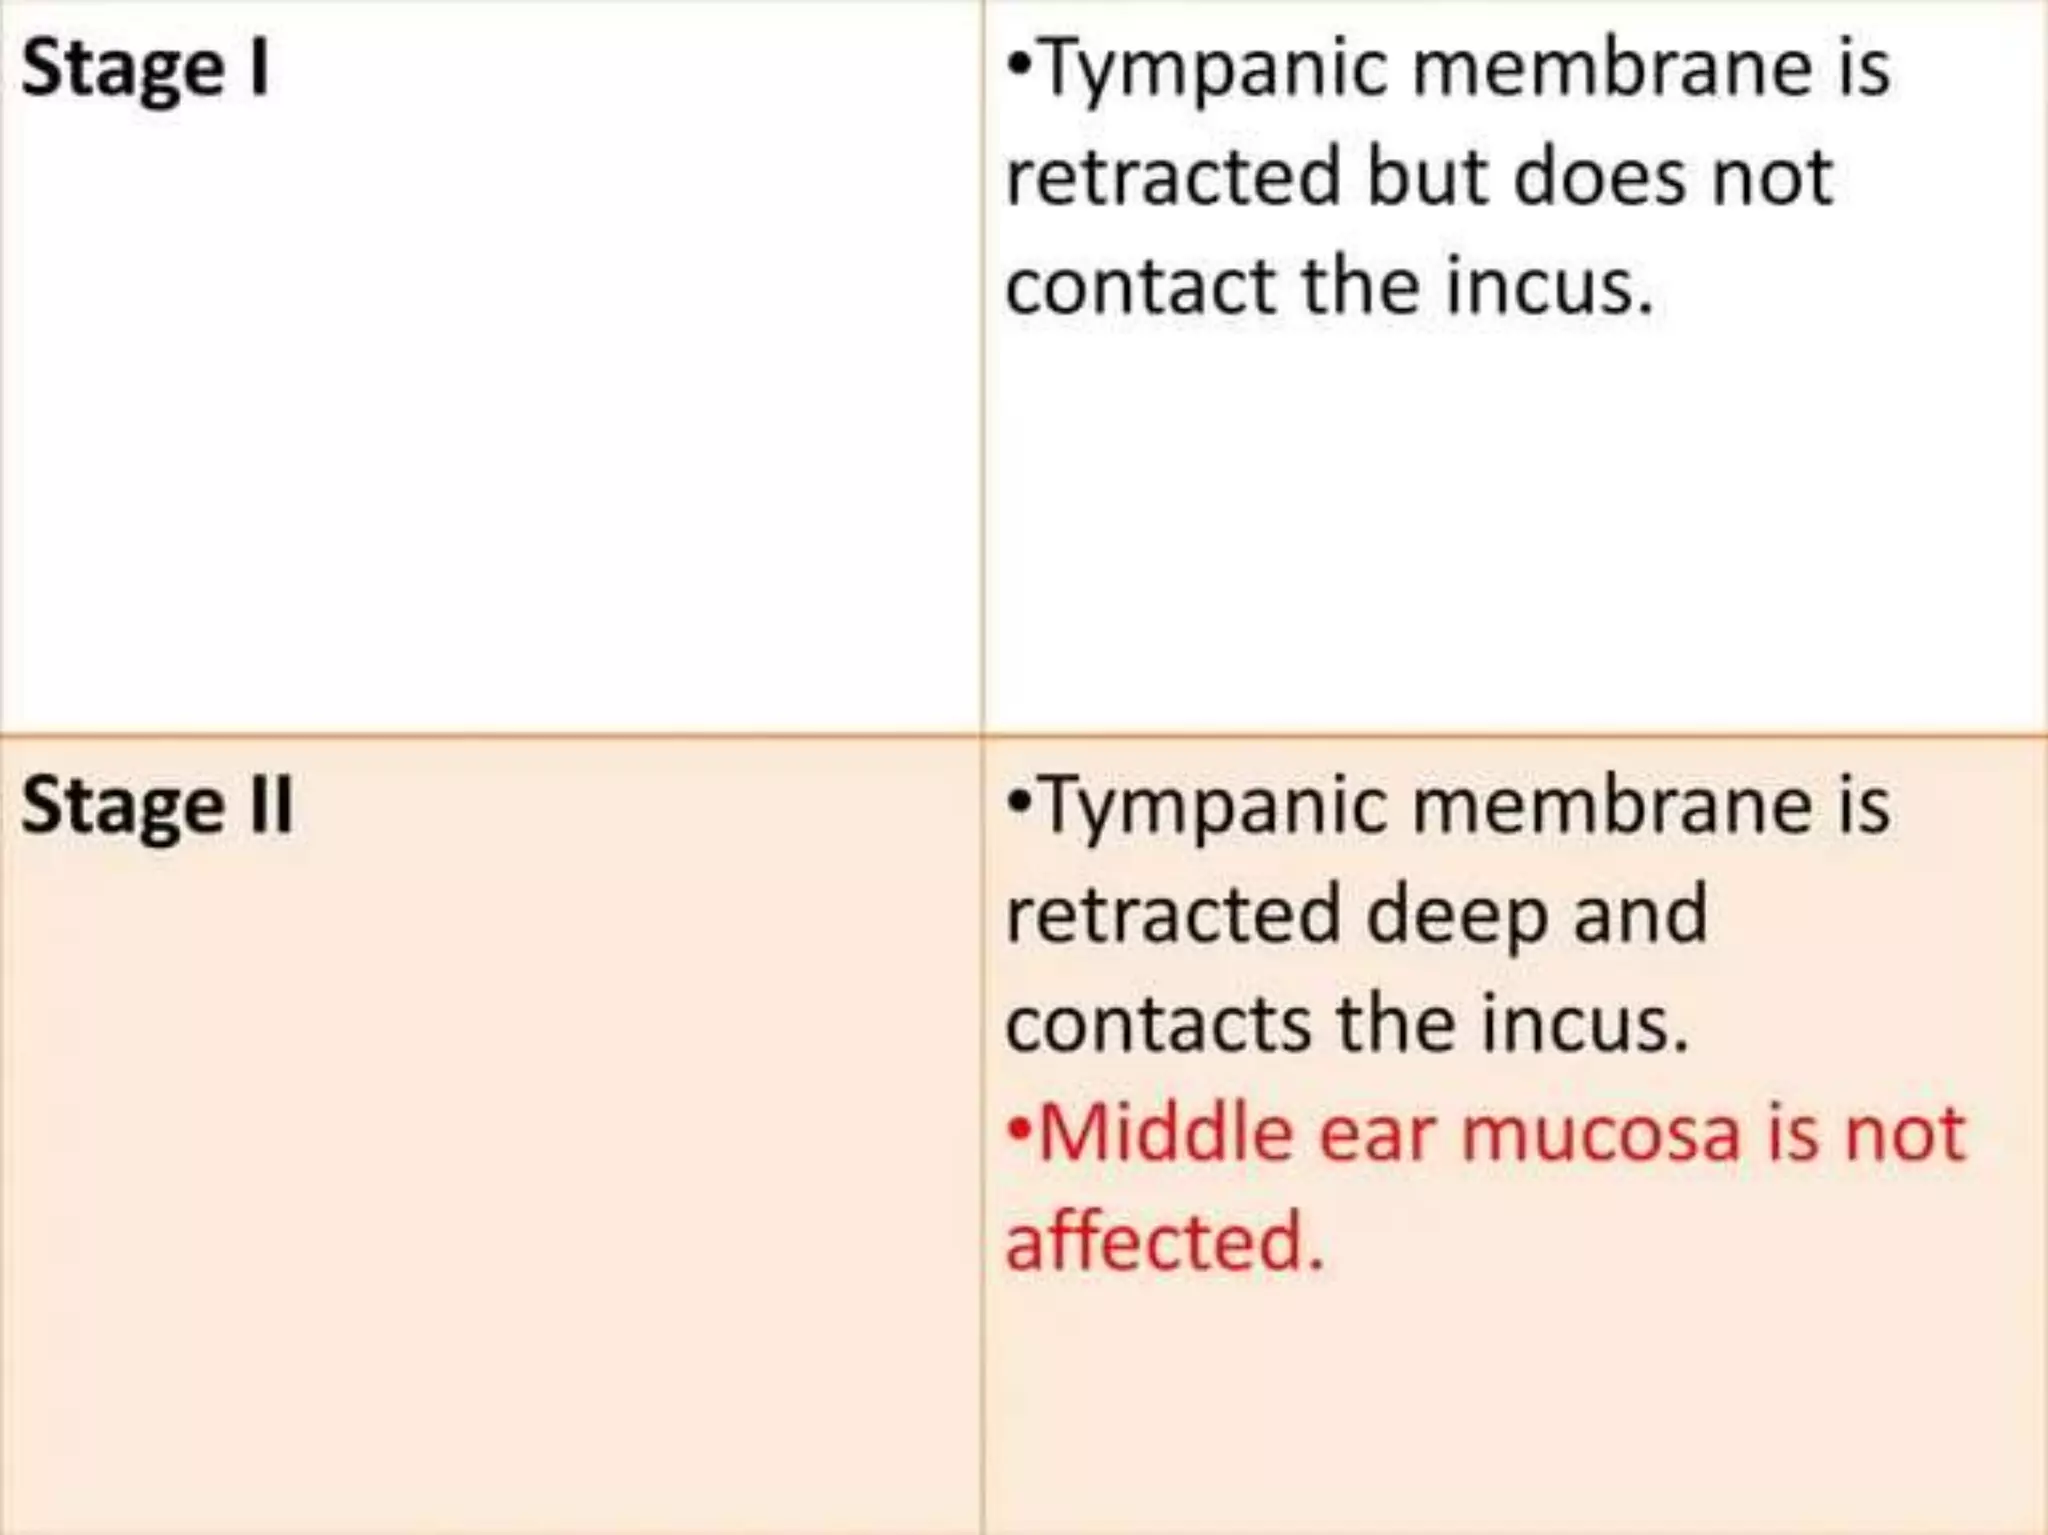

Chronic otitis media is a chronic inflammation of the middle ear and mastoid cavity that presents with recurrent ear discharge through a perforated eardrum. It has several subtypes depending on the state of the eardrum perforation and epithelium. It can be caused by prior acute otitis media, genetics, environment, eustachian tube issues, gastroesophageal reflux disease, craniofacial abnormalities, or immune deficiency.